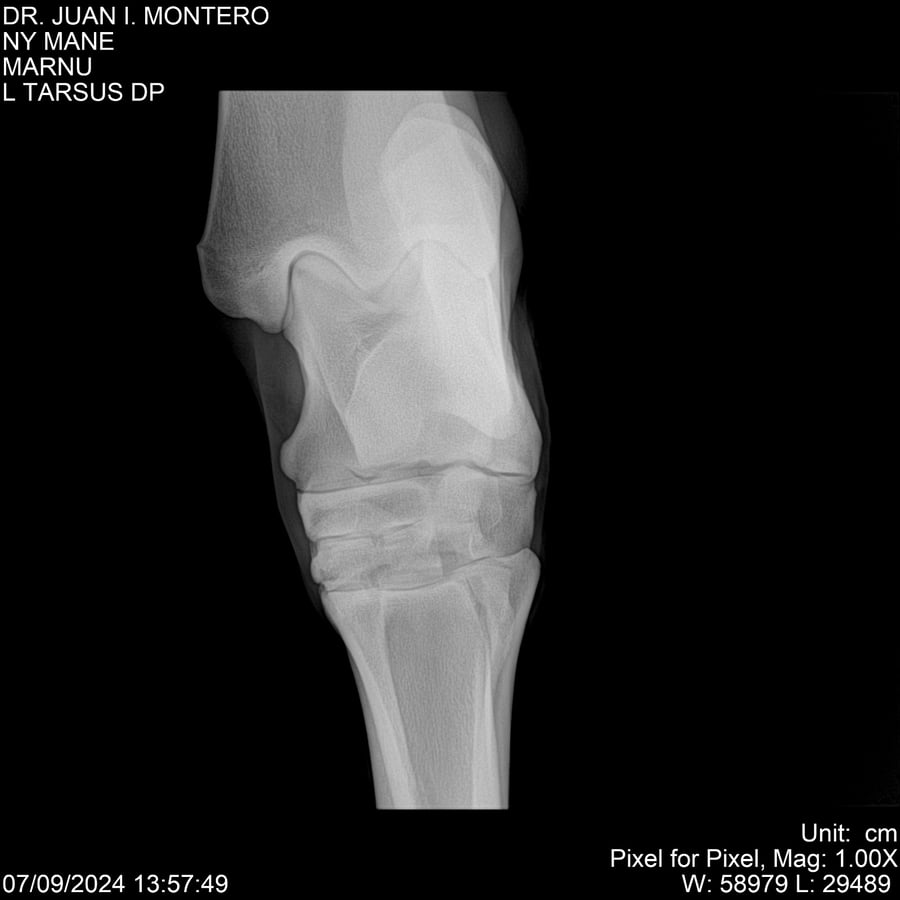

LOTE 20, NY MANE Lote Anterior Volver al remate Lote Siguiente Ficha Contacto Montevideo - Ficha del Lote Identificador: #282520 Categoría: Yeguarizos 76 Visualizaciones ClicData Contacto Empresa: Abelenda N. R., Walter Hugo Nombre*: Teléfono* : E-mail* : Mensaje Enviar Registrese gratis Este contenido Exclusivo está disponible sólo para usuarios registrados Ingresar